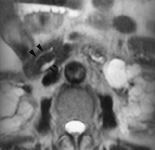

ABCFig. 9.--Páncreas divisum. A) Reconstrucción MIP a partir de secuencia HASTE en proyección coronal; se visualiza el conducto pancreático ventral (flechas) y el conducto pancreático dorsal (punta de flechas) sin conexión de ambos. B) Mismo detalle en un corte axial de una secuencia HASTE. C) En la CPRE sólo se ha opacificado el conducto ventral (flechas).

El páncreas divisum es una anomalía congénita que resulta del fallo de fusión entre páncreas ventral y dorsal durante la sexta-octava semanas de gestación. La prevalencia de esta anomalía en autopsias es del 4-14% (3) y por CPRE es del 2-8% (4). En muchos casos la ausencia de fusión es completa y no existe comunicación entre páncreas ventral y dorsal (Figs. 9A, B y C). También existe una forma incompleta en la que persiste un fino conducto entre ambos, siendo el dorsal predominante (Fig. 10). La importancia clínica del páncreas divisum es controvertida; algunos autores piensan que se trata de una variante de la normalidad y que no tiene relación con pancreatitis (5). Otros autores creen que esta anomalía puede inducir episodios recurrentes de pancreatitis y que éstos se beneficiarían de una esfinterectomía de la papila menor (6).